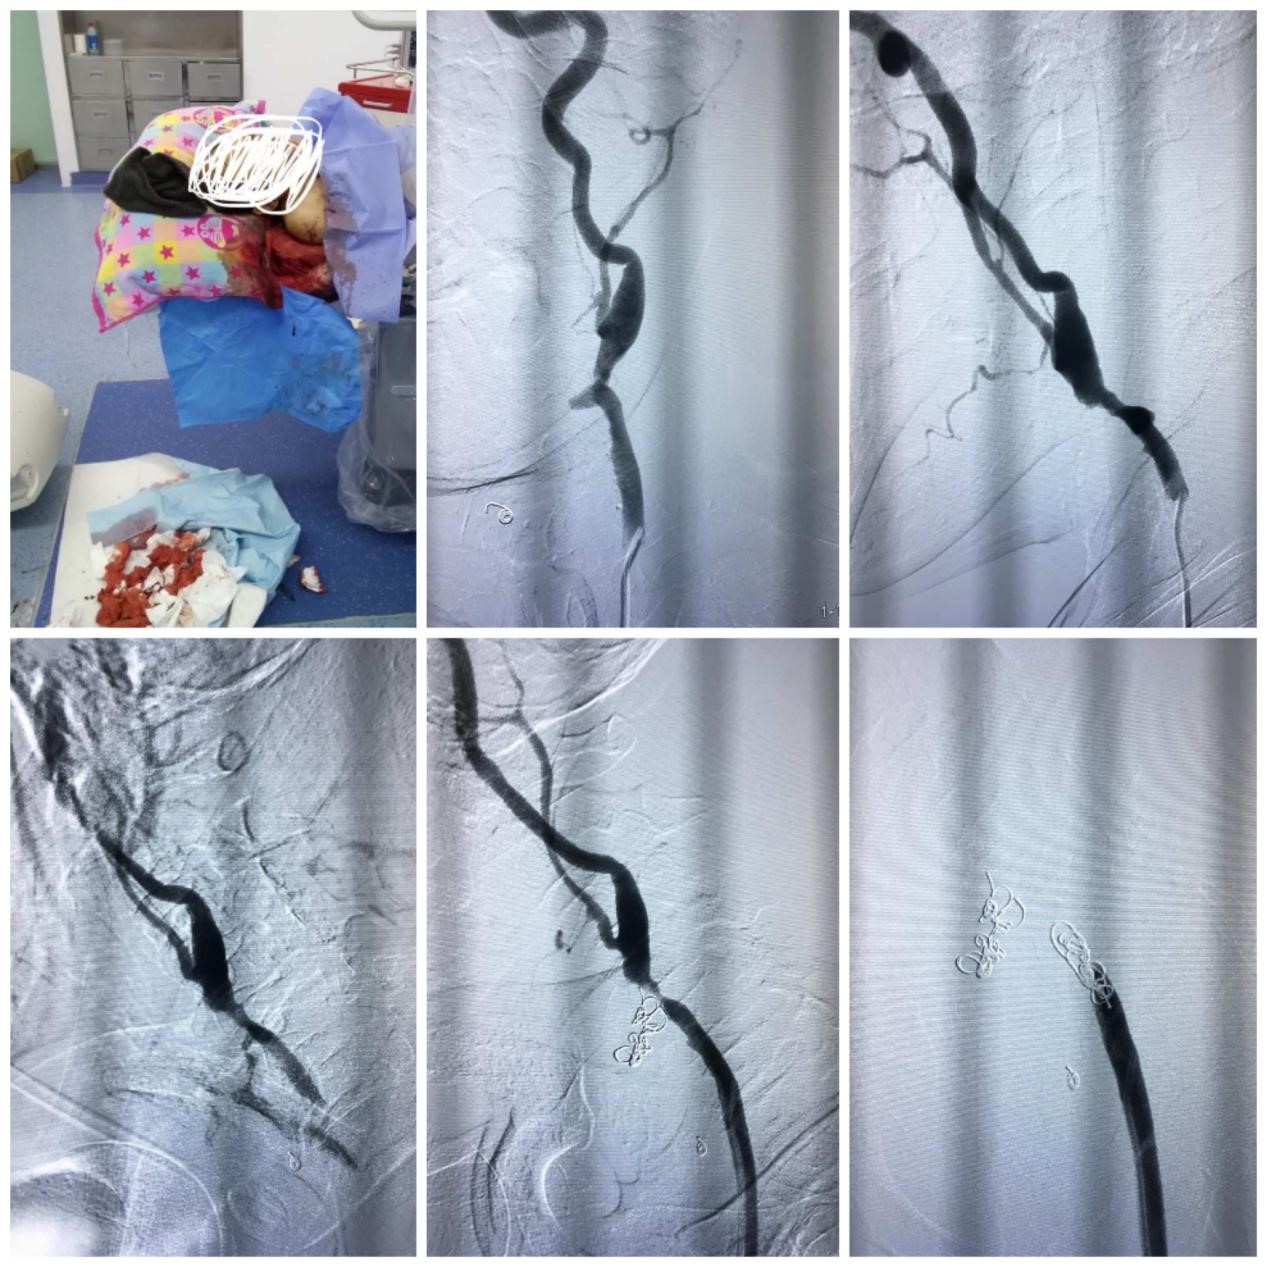

據(jù)了解,患者王先生(化名),58歲,確診鼻咽癌一年,患者經(jīng)規(guī)范放化療治療后,清明節(jié)當天凌晨,前后三次鼻出血,大量鮮血由口鼻噴涌而出,患者一度因失血過多昏迷,出血量1500ml,急診測血壓73/53mmHg,這樣兇險的出血,隨時會導致死亡,醫(yī)生當即決定給患者作左側(cè)鼻腔填塞壓迫止血,在升壓藥物維持下緊急開展介入手術(shù)。

術(shù)中,患者術(shù)中不間斷口鼻出血,情緒激動,李忠輝主任一邊安撫患者,一邊進行手中的操作,通過導管導絲交換技術(shù),終于發(fā)現(xiàn)病變血管,造影示左側(cè)頸內(nèi)動脈主干變細,可見假性動脈瘤形成,“因為患者做過放化療,因此勁內(nèi)動脈就變得比正常人更細、更窄了,變細的頸動脈破了之后,出血量非常大,幸運的是患者右側(cè)血管代償很理想,血管變粗,遂行頸內(nèi)動脈主干栓塞。如果是正常頸動脈被栓塞的話,患者很有可能會發(fā)生偏癱”李忠輝主任表示。經(jīng)過緊張的手術(shù),成功為患者止血,術(shù)后患者血壓穩(wěn)定,未發(fā)生偏癱等癥狀,患者于近日出院。

術(shù)后隨訪,患者神清語利,行動自如,未出現(xiàn)肢體活動障礙,談及這次經(jīng)歷,王先生仍舊驚魂未定,同時也對救命恩人李忠輝主任及屈振杰業(yè)務(wù)副主任表示了由衷的感謝!